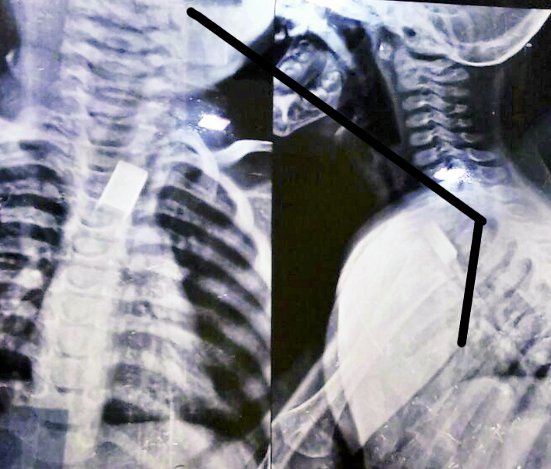

बारां निवासी एक साल का बच्चा घर पर खेल-खेल में स्टेपलर की पिन खा गया। तबीयत बिगडऩे पर परिजन उसे दादाबाड़ी स्थित गेस्ट्रो केयर सेंटर लाए। यहां एण्डोस्कोपी पद्धति से दस मिनट में पिन बाहर निकाले गए। बच्चे की हालत अभी ठीक है।

बारां निवासी बृजराज वैष्णव ने बताया कि 15 अक्टूबर को सुबह बड़े पुत्र के स्कूल के बैग से स्टेपलर पिन सेट गिर गया था। उसी समय छोटा पुत्र दक्ष (1) ने खेलते-खेलते उसे उठाकर मुंह में खा लिया। अचानक पता चलने पर उसे बारां जिला अस्पताल लेकर गए। वहां चिकित्सक को दिखाया, लेकिन पिन नहीं निकाला। तब 16 अक्टूबर को उसे लेकर कोटा गेस्टो केयर सेंटर पहुंचे। यहां जांच में उसके पेट में स्टेपलर पिन दिखाई दिए।

इधर, सेन्टर के निदेशक डॉ. एडी खिलजी ने बताया कि जांच में पिन बच्चे के पेट में दो भागों में बंट गए थे। इससे पिन पेट में फैल गई थी। पहले बच्चे को बेहोश किया और स्वयं व डॉ. कपिल गुप्ता ने मिलकर एण्डोस्कोपी पद्धति से स्टेपलर पिन निकाले। उन्होंने बताया कि आमतौर पर बच्चे सिक्के, कील, घड़ी व बैट्री के छोटे सेल निगलने के केस आते हैं, लेकिन एेसा केस पहली बार आया है। उन्होंने बताया कि बच्चे के पेट में पिन फंसे रहने से आंतों में छेद होने का खतरा बना रहता। खाने की नली में फंस जाने पर नली में छेद हो सकता है। आंतें भी प्रभावित हो सकती हैं। इससे मृत्यु की भी संभावना बन सकती है।